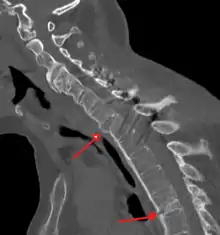

Fracture of the T5 and C7 vertebra due to trauma in a person with ankylosing spondylitis as seen on a CT scan

Prognosis is related to disease severity.[9] AS can range from mild to progressively debilitating and from medically controlled to refractory. Some cases may have times of active inflammation followed by times of remission resulting in minimal disability while others never have times of remission and have acute inflammation and pain, leading to significant disability.[9] As the disease progresses, it can cause the vertebrae and the lumbosacral joint to ossify, resulting in the fusion of the spine.[47] This places the spine in a vulnerable state because it becomes one bone, which causes it to lose its range of motion as well as putting it at risk for spinal fractures. This not only limits mobility but reduces the affected person's quality of life. Complete fusion of the spine can lead to a reduced range of motion and increased pain, as well as total joint destruction which could lead to a joint replacement.[48]

Osteoporosis is common in ankylosing spondylitis, both from chronic systemic inflammation and decreased mobility resulting from AS. Over a long-term period, osteopenia or osteoporosis of the AP spine may occur, causing eventual compression fractures and a back "hump".[49] Hyperkyphosis from ankylosing spondylitis can also lead to impairment in mobility and balance, as well as impaired peripheral vision, which increases the risk of falls which can cause fracture of already-fragile vertebrae.[49] Typical signs of progressed AS are the visible formation of syndesmophytes on X-rays and abnormal bone outgrowths similar to osteophytes affecting the spine. In compression fractures of the vertebrae, paresthesia is a complication due to the inflammation of the tissue surrounding nerves.